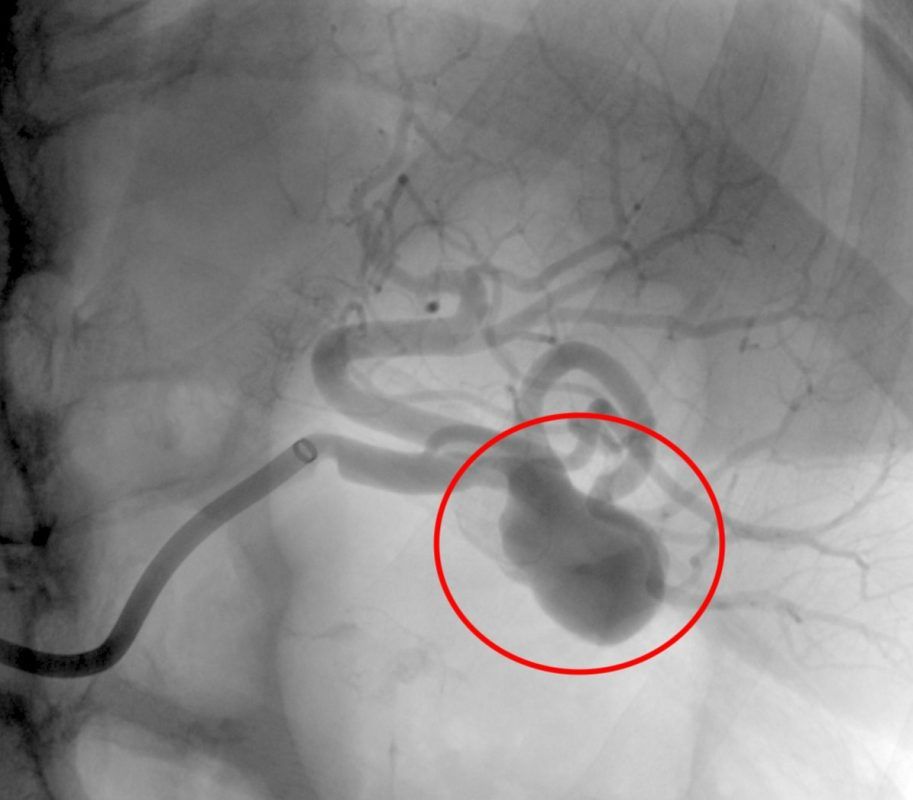

Apresento um caso de embolização de um aneurisma sacular de artéria esplênica.

Optou-se pelo emprego de molas em detrimento de stent revestido (stent graft) devido a presença de um colo relativamente estreito e à localização do aneurisma ser no terço distal da artéria esplênica havendo bifurcação da mesma logo após ao aneurisma, o que levaria à provável perda de um dos ramos distais.

As angiografias de controle evidenciaram completa exclusão do aneurisma esplênico com manutenção integral da irrigação do baço.